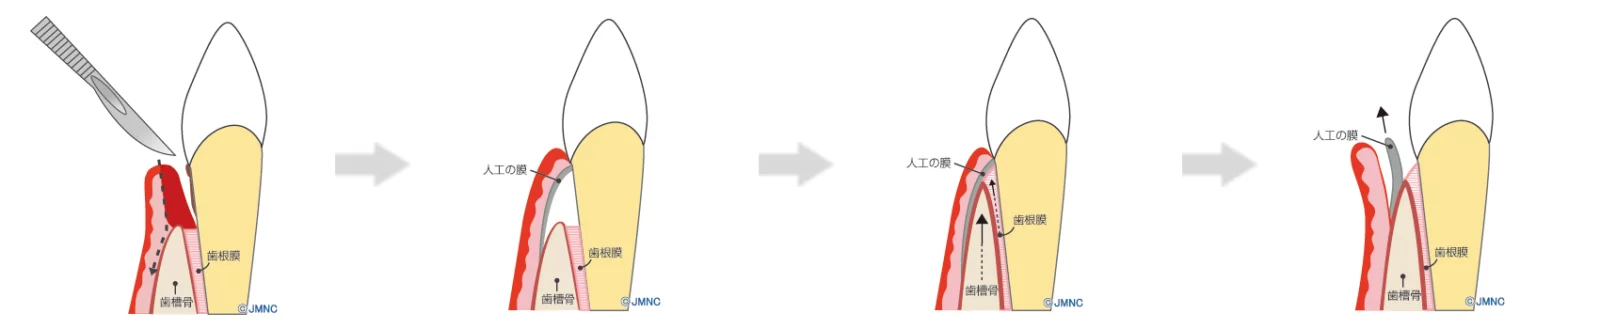

適切な歯周病治療を行うと、失われた骨や歯肉は時間をかけて徐々に回復します。あまり知られていないのですが、骨には自然に修復する力があります。

しかし、何も対策をしないで放置しておくと、骨の再生は期待できないことが多いです。特に、歯肉は骨よりも速くに再生するため、本来骨が再生すべき場所を埋めてしまい、結果として骨の再生が妨げられることがあります。

このような状況を避けるために、当院では「GTR法」を採用しています。この治療法は、再生すべき骨の部分を「メンブレン」と呼ばれる特殊な膜で覆い、歯肉の成長を抑制しながら骨の再生を促進します。この方法により、骨と歯肉の回復を適切に管理し、より健康な口内環境へと回復させることが可能となります。